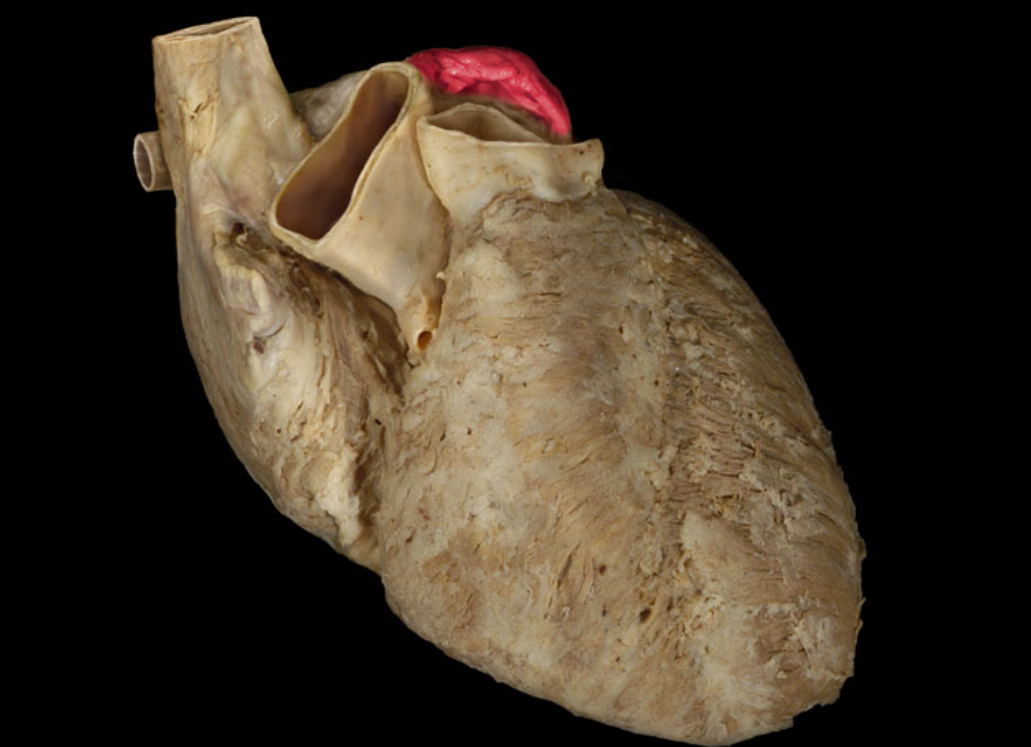

Arch of aorta

Brachiocephalic trunk

Inferior vena cava

Left auricle

Pulmonary trunk

Right auricle

Superior vena cava